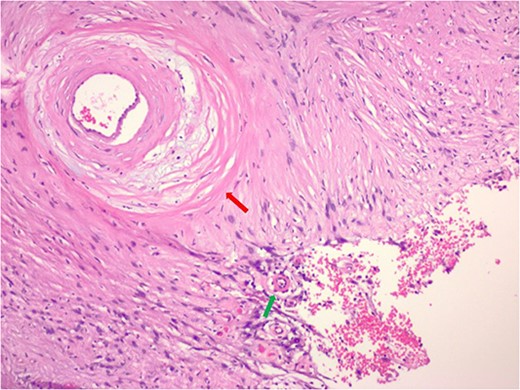

Hematoxylin and eosin stain pathologic slide of ancient schwannoma showing hyalinizing vessel (green arrow) and cystic degeneration (red arrow) characteristic of ancient changes.